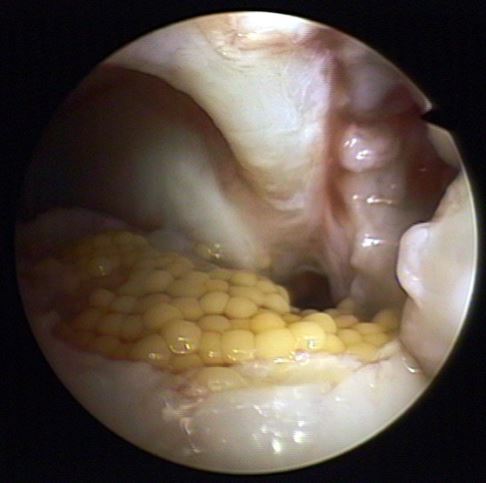

Minimalinvasiv werden gesunde Knorpelzellen des Patienten gewonnen und außerhalb des Körpers im Labor vermehrt. In einem zweiten Eingriff bringt der Arzt die autologen (körpereigenen) Knorpelzellen in die geschädigte Stelle des Knorpels ein. Die Knorpelverletzung wird mit den Knorpelkügelchen bedeckt, die nach wenigen Sekunden am Untergrund haften.

Die Knorpelverletzung ist nach dem ca. 30 Minuten dauernden minimalinvasiven Eingriff mit den haftenden Knorpelzellkügelchen abgedeckt. Nach dem Eingriff ist ein dreitägiger stationärer Krankenhausaufenthalt erforderlich. Nach 6 Wochen kann der Patient das Sprunggelenk teilbelasten, nach 3 Monaten voll belasten. Der Langzeiterfolg der Knorpeltransplantation ist gut.